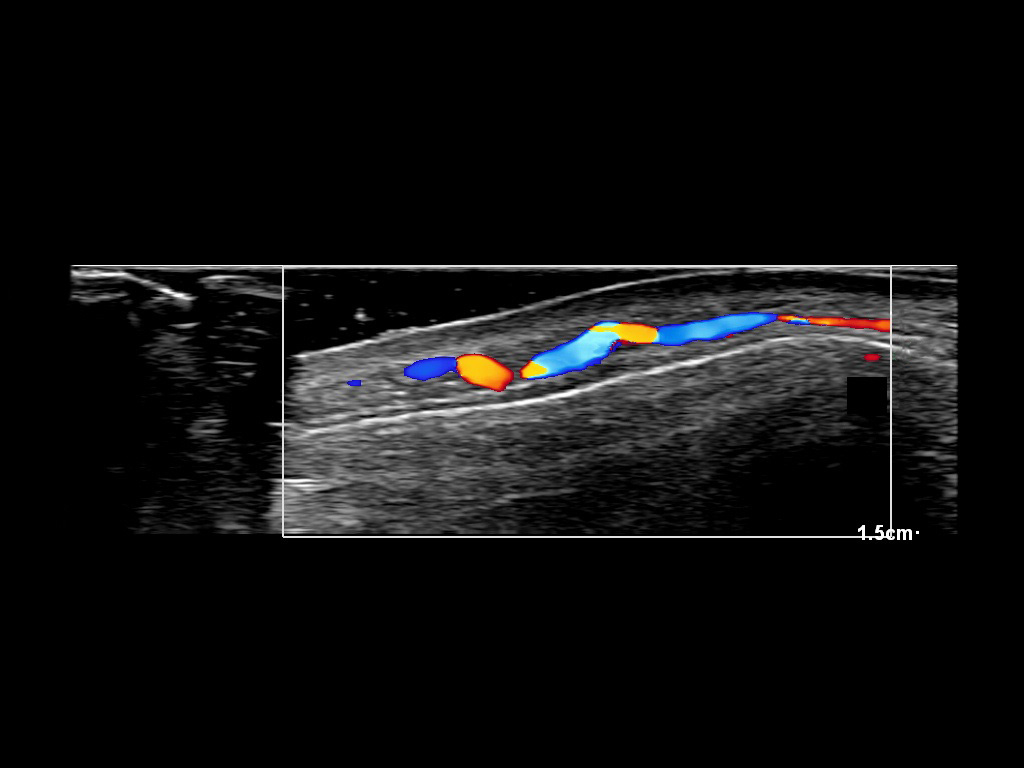

In this section you will learn more about the different layers of the face with the use of ultrasound. When you click on the secondary ultrasound image, you will see the different structures as an overlay. This will help to train yourself to recognize the different layers of the face.

Study the first image to recognize the different layers. If you are sure about the layers, swipe to the second image to view the answer (if applicable).